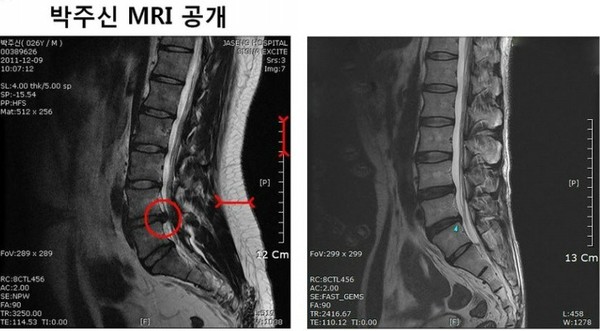

한편, 강 의원이 전날 박원순 시장 아들의 MRI 사진을 공개하자 인터넷은 한바탕 난리가 났다.

사진을 접한 네티즌들은 “바짝 마른 박주신씨의 몸과 MRI 사진이 같은 사람의 것이라고는 상상하기 힘들다”, “누가 봐도 다른 사람의 사진임이 분명하다”는 반응을 보였다.

강 의원은 일각에서 주장하는 ‘MRI 진위 논란’에 대해 “문제의 MRI 필름을 놓고 박주신의 것이 맞는지 입증하라고 하는 말도 있는데 오늘 병무청의 한 관계자로부터 당시 제출된 MRI 필름과 어제 공개한 사진이 동일하다는 제보를 받았다. 출처 또한 확실하다. 이에 대해서는 곧 밝힐 기회가 있을 것”이라고 말했다.

- ▲ 무소속 강용석 의원이 공개한 박원순 시장 아들 박주신의 MRI 사진(좌) 키 173cm 63kg 박주신과 같은 체형을 가진 허리디스크 환자의 MRI 비교. 전문의들은 좌측 사진에 대해 90kg 이상 고도비만 환자의 것이라는 분석을 내놨다. ⓒ강용석 의원실